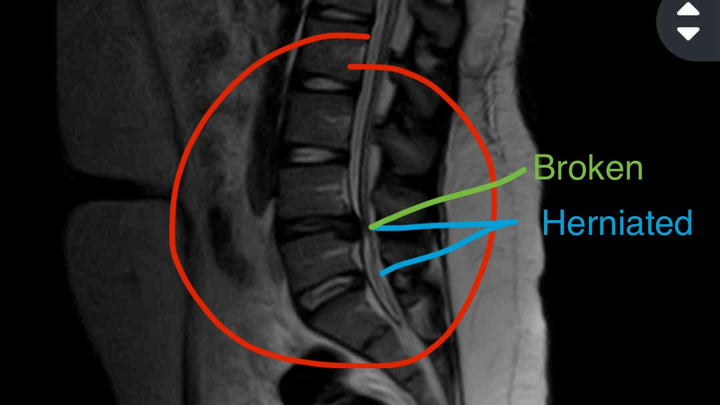

Needing help with medical costs after being hospitalized! While volunteering, Lake sustained a back injury that later became severe. She tried resting for a few weeks, thinking it was just a pulled muscle. During this time, she developed a kidney infection that progressed into the early stages of sepsis, making the pain unbearable. After going to the hospital for treatment, things only got worse. Although the kidney infection had been treated, the back pain hadn't gone away and was starting to spread to Lake's legs. After going back to the hospital for an MRI, we found out that she had two herniated discs in her back, one of them having been broken. With how bad the broken disc had gotten, an emergency surgery was imminent.